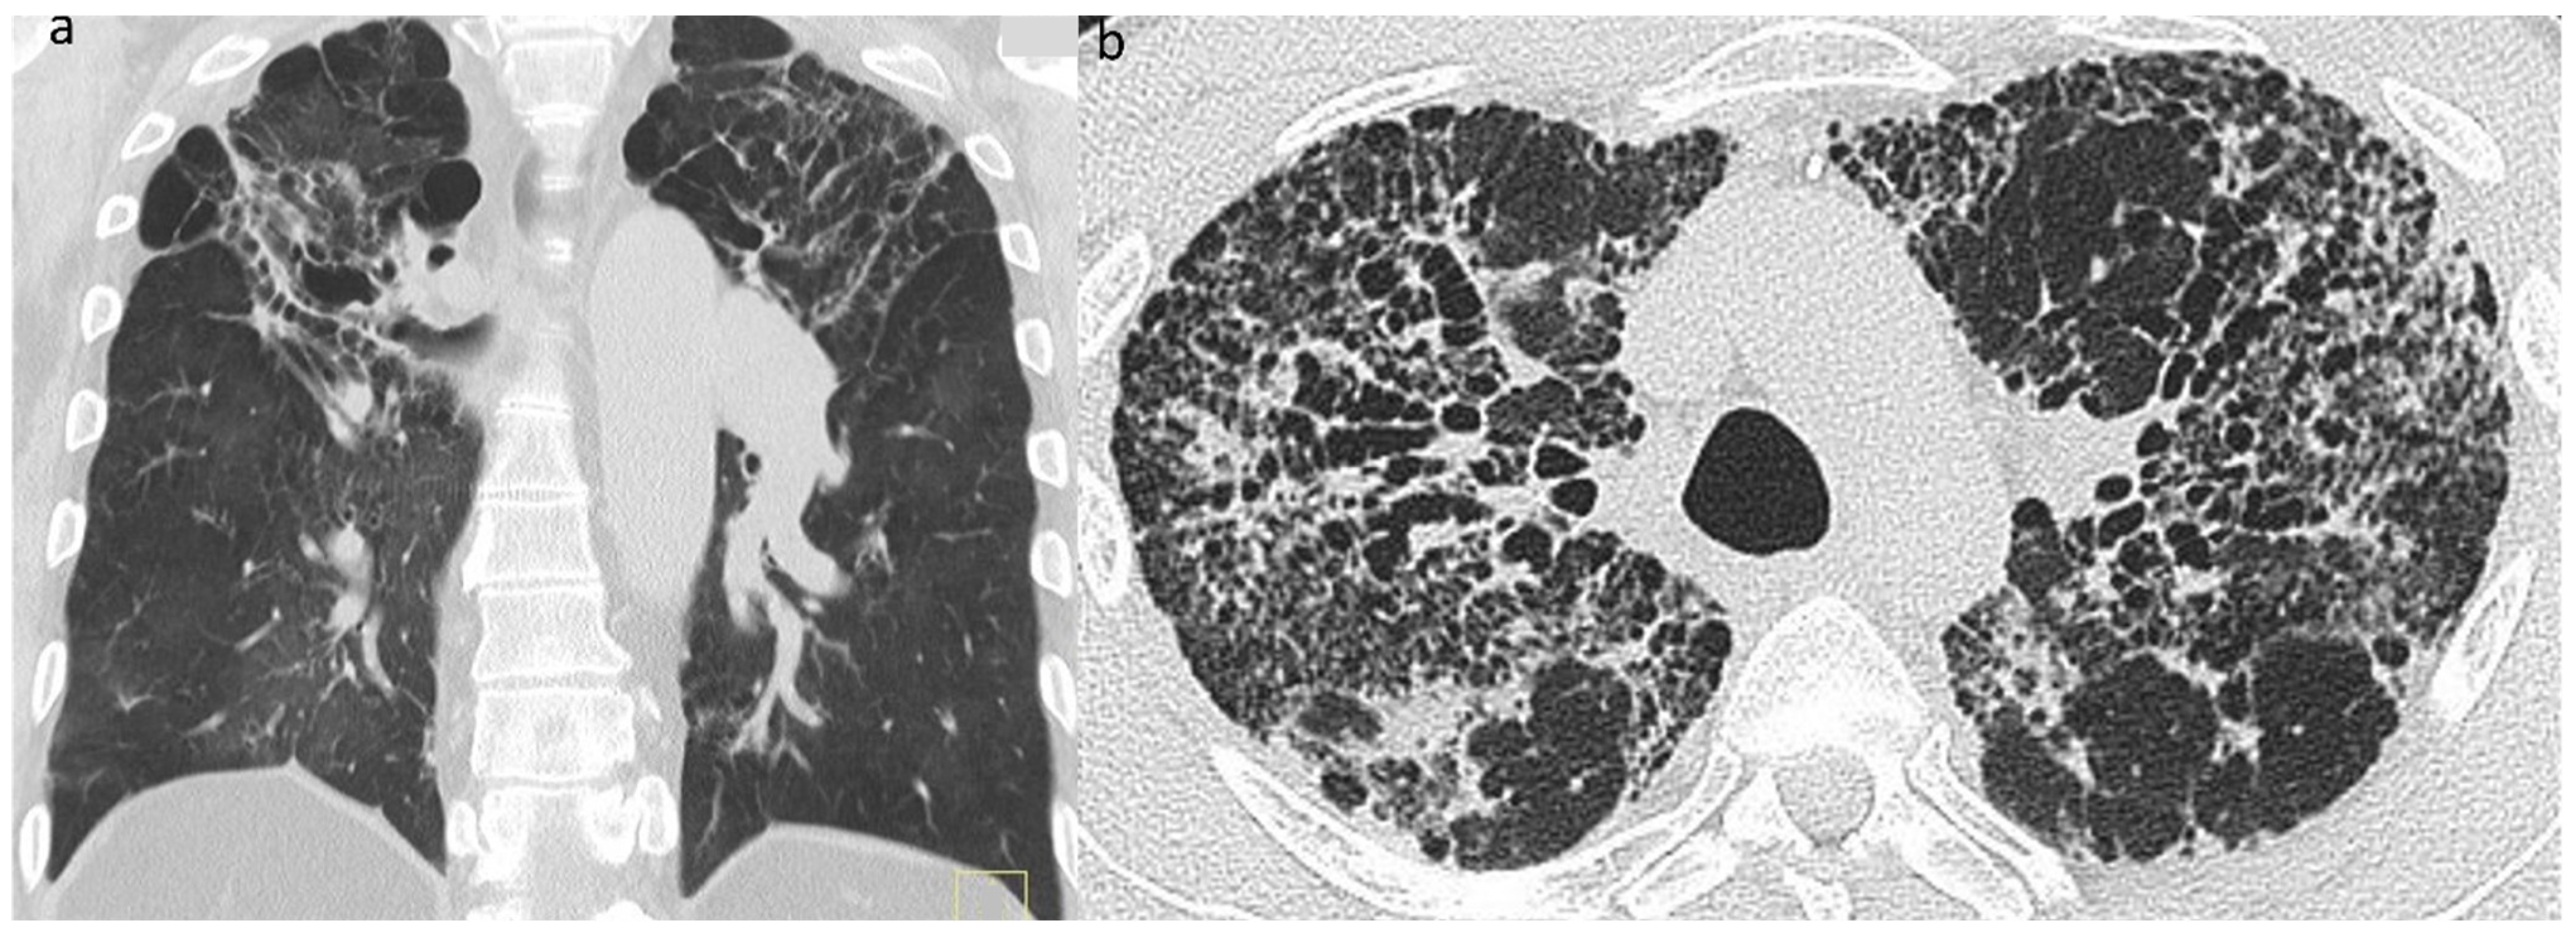

Of the variety of CT patterns reported in sarcoidosis, nodular infiltrates are most likely to improve or resolve at follow-up [41]. Additionally, peribronchovascular thickening, consolidation and ground-glass opacification also have the potential to resolve completely [41,49,130], particularly with treatment [49] (Figure 8a,b). While linear opacities may clear, Murdoch and co-workers found an increased likelihood of progression over time and more so than with other morphologic features [41]. The natural history of ground-glass opacities is more difficult to predict and this CT pattern is a poor predictor of both disease activity and prognosis [41,49]. In part, this might be due to the non-specificity of CT ground-glass opacification which might indicate ‘active’ (and therefore potentially reversible) granulomatous inflammation or irreversible fine fibrosis below the limits of CT resolution [50]. CT abnormalities tending to indicate irreversible disease include reticulation, architectural distortion, honeycombing and traction bronchiectasis/bronchiolectasis. However, while some patients inevitably progress despite treatment, relative stability over time is more common in sarcoidosis-related ILD than in overtly progressive fibrotic DILDs [108].

Figure 8.

(a,b): Reversible disease in sarcoidosis. Targeted images of the left mid-zone showing the resolution of multiple random micronodules over time in (a) 2015 and (b) 2017.